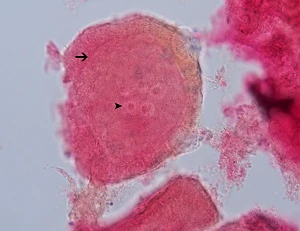

Adult Inermicapsifer madagascariensis measure 24—42 cm long and 3 mm wide with up to about 360 proglottids. The unarmed scolex is small and round with four simple suckers. The unilateral genital pore opens in the middle of the lateral margin of the proglottids (versus similar Raillietina spp., which open in the anterior quadrant). Gravid proglottids shed in feces are rounded, white, and usually motile. They are filled with egg capsules, creating a “mosaic” or reticulated appearance when examined microscopically. Egg capsules are roughly polygonal with a transparent outer portion and a darker center, and contain 4—15 individual eggs.

Inermicapsifer spp. egg capsules are roughly polygonal with a transparent outer portion and a darker center, containing 4—15 individual eggs. They are similar in appearance to those of Raillietina spp.